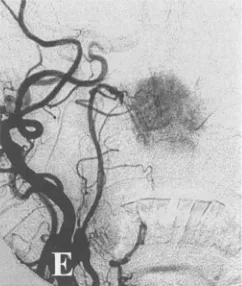

血管造影显示肿瘤主要由咽升动脉分支供血(E)。咽升动脉是滋养软腭、咽鼓管、口鼻咽及部分椎旁骨骼肌的重要血管,同时在后组颅神经、鼓室、部分后颅窝硬膜也有其分布,手术中对血管的处理和保护极其重要